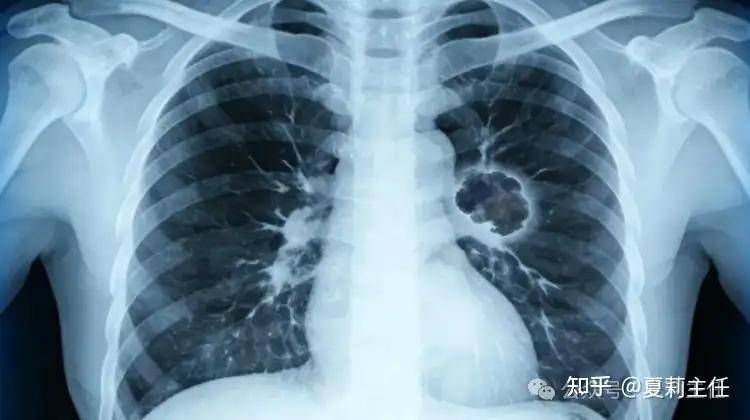

昨天接诊了一个癌症病人,真的很不容易,对方刚到退休年纪,眼看就能安享晚年、领取退休金,却因持续咳嗽、胸痛就医,最终被确诊为肺癌晚期,还伴随脑转移,连手术的机会都没有。得知这个结果,患者家属瞬间崩溃,患者和家人红着眼眶,一遍遍追问夏主任:“还能治吗?怎么治才有用?”我轻轻拍了拍他们的背,轻声安抚:“先别慌,咱们要先稳住,一起找最合适的办法。”

过去人们对肺癌晚期的理解大多是“扩散了”,“治不好了”,但现在的医学已经不再是几十年前的水平。近年来晚期肺癌患者的5年生存率已从个位数提升至20%左右,部分人群甚至能实现“带瘤生存”。

这不是奇迹,而是精准治疗,如靶向药物、免疫治疗、精准放疗等新技术的成果。部分晚期患者精准治疗后,病情可得到长期控制,生活质量大幅提升。